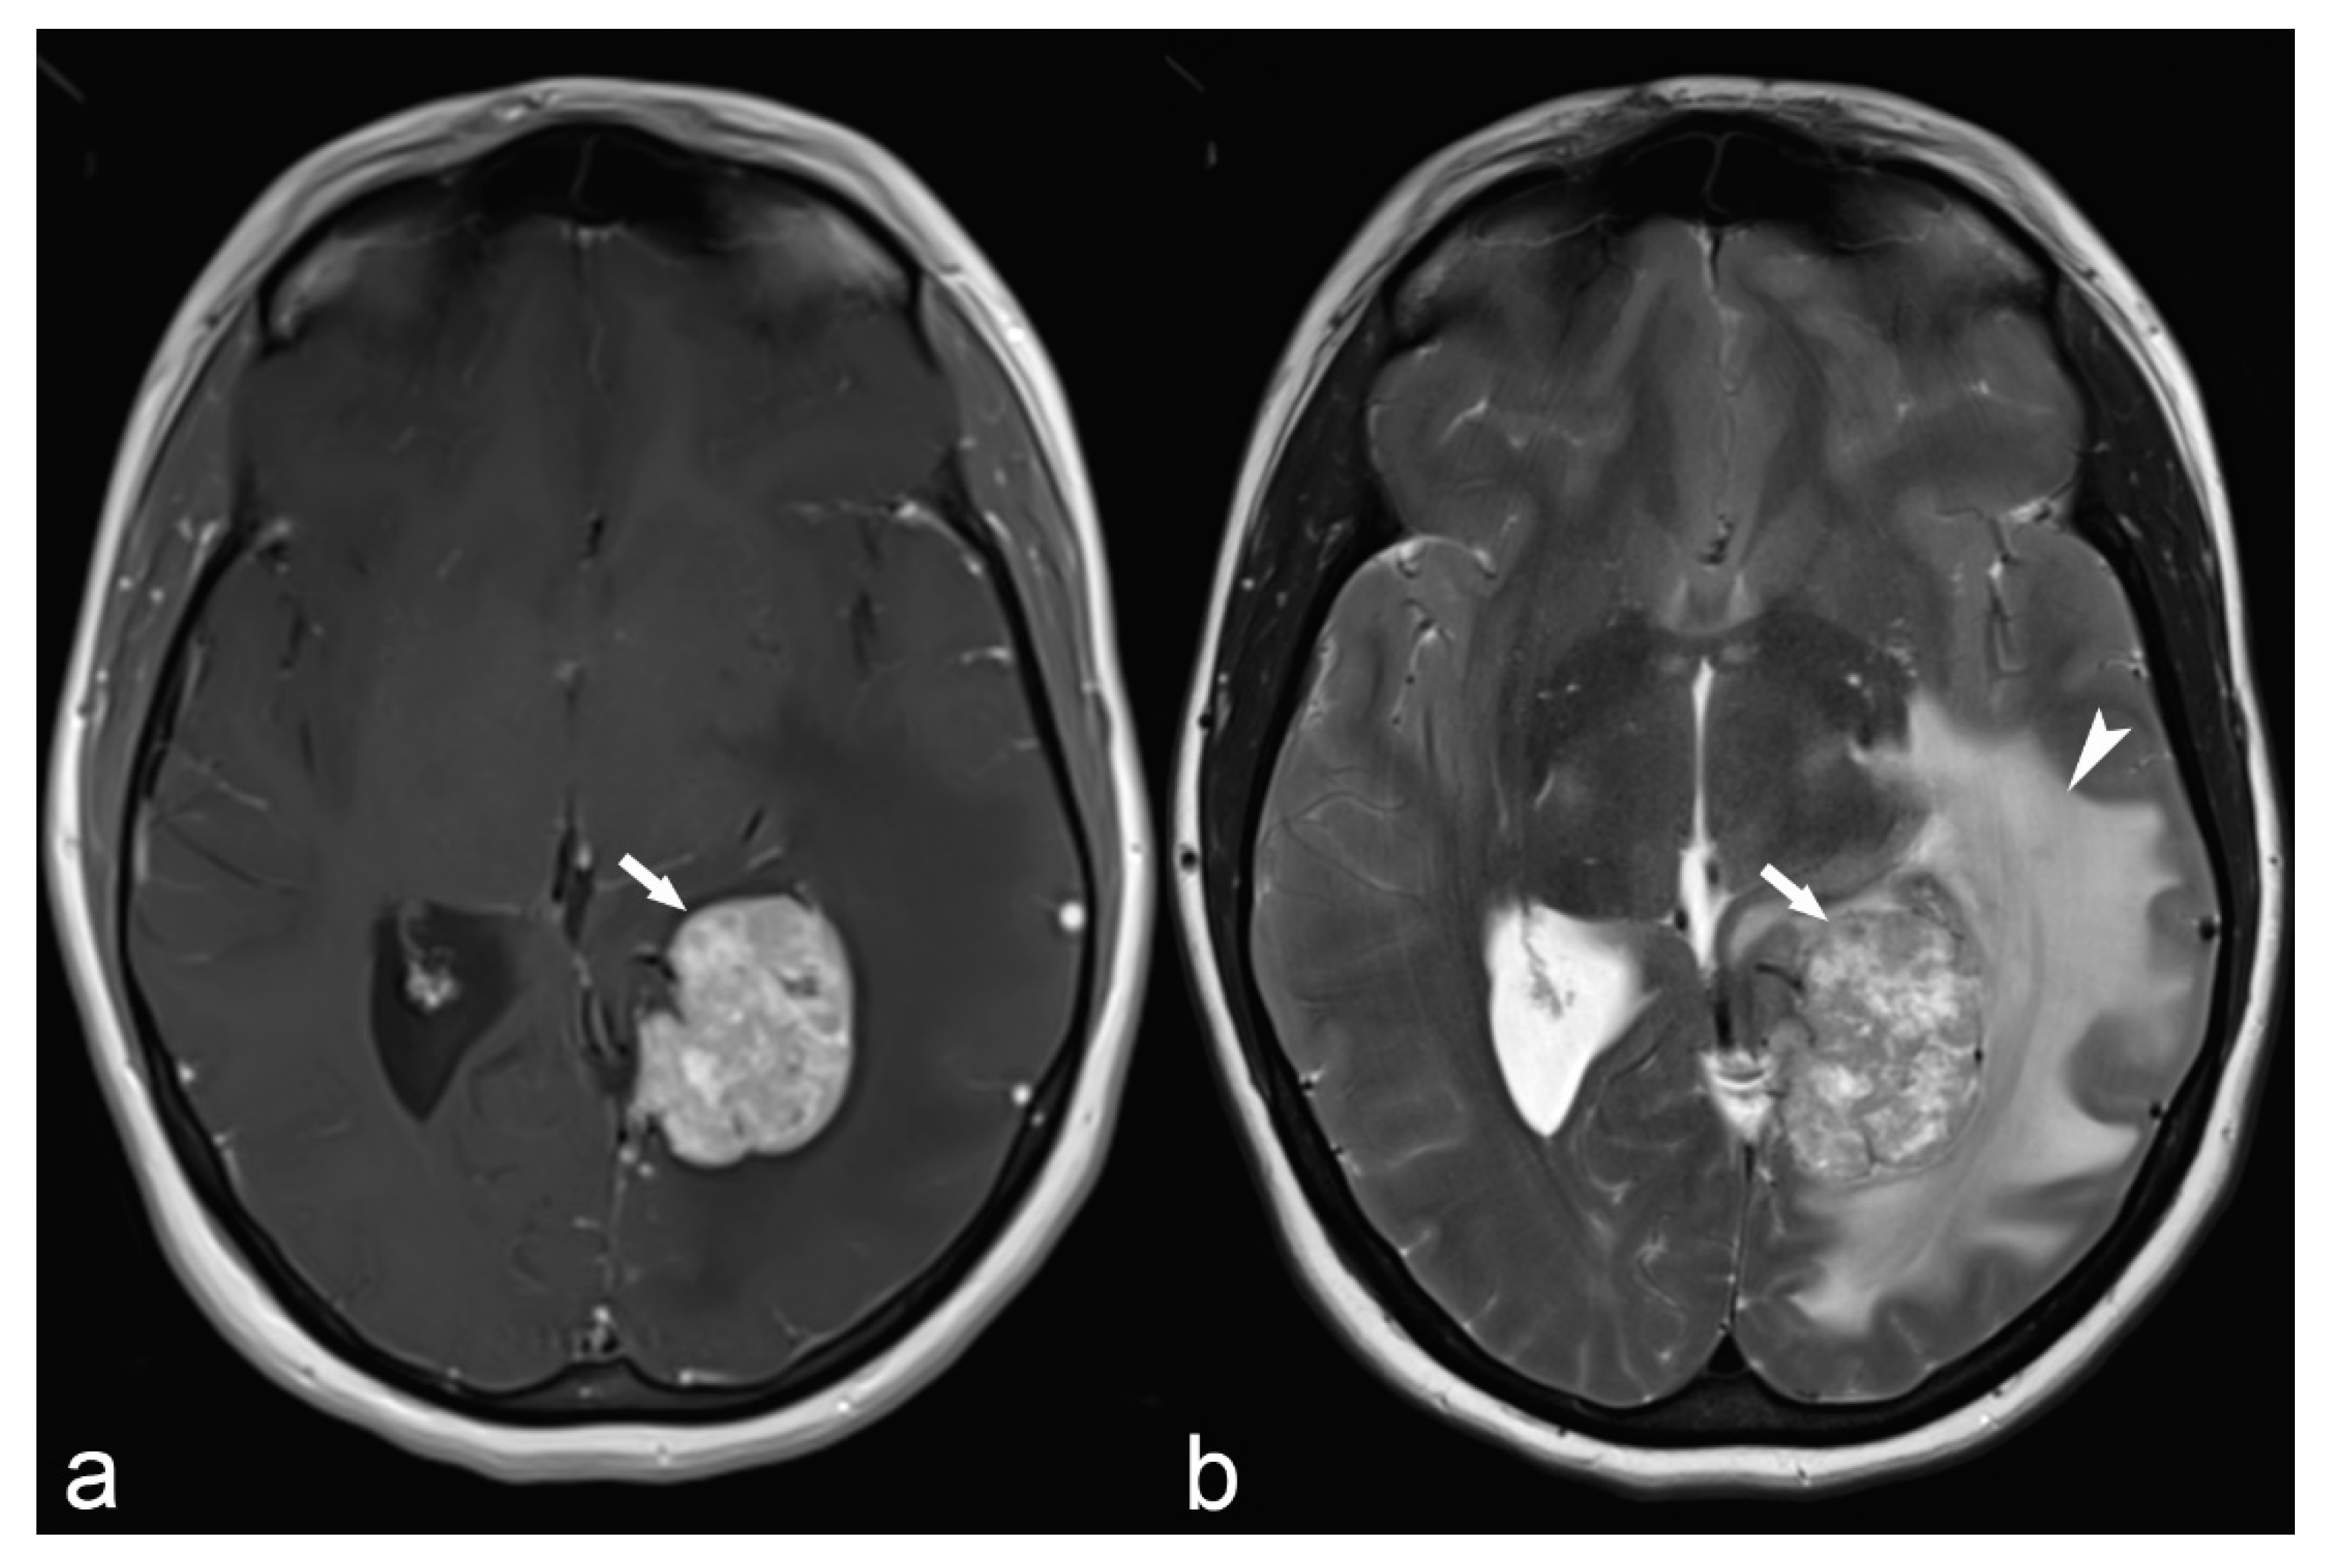

Figure 535 From Focal Epileptogenic Lesions Semantic Scholar

Structural Magnetic Resonance Imaging In Epilepsy Springerlink

Focal Epileptogenic Lesions Sciencedirect

Children Free Full Text Morphological And Advanced